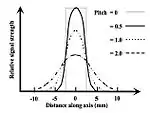

Helical CT

- Helical scanning, as illustrated in panel (d) of Figure 17.15.1, was developed on the basis of continuous movement of the patient table along the cephalocaudal direction (z-axis) of the scanner. Axial slices were generated through interpolation along the z-axis prior to Filtered Back-Projection (FBP) reconstruction. Table speeds of 1-10 mm/s and complete 360° rotations were achieved in half a second or less with the fan beam collimated to 1-10 mm thick. A new scanning parameter called the Pitch was introduced, which defined the ratio of the table movement distance in a single rotation to the slice thickness. A table movement distance of 10 mm and a slice thickness of 10 mm would therefore generate a pitch of unity. Pitch values of 0.5-2 were used depending on the desired spatial resolution along the z-axis, with those less than one, e.g. 0.8, providing adequate over-lapping slices for 3D visualizations. No gaps in the data set occurred as the anatomy was being scanned, which can be contrasted with conventional axial scanning where inter-slice gaps result unless contiguous slices are specifically chosen to be scanned.

- Because of the relative motion between the patient table and the gantry, the effective slice width given by the Slice Sensitivity Profile (SSP) was greater than the nominal slice width because the slice profile is blurred by a convolution with a triangular profile attributable to the table motion - see Figure 7.15.4. Software advances using z-interpolation techniques were then applied to minimise this broadening of the SSP[38]. Linear Interpolation could be applied, for example, to both 180o and 360o sequences from adjacent helical scans to give the so-called 180LI and 360LI, or Slim and Wide, processing algorithms. However, regardless of the interpolation technique employed increasing the pitch led to increased effective slice widths.